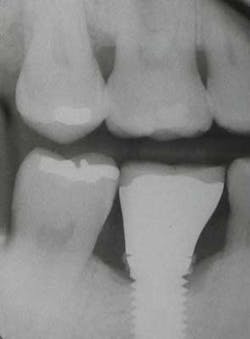

Fig. 1: Radiograph retained cement causing peri-implantitis.